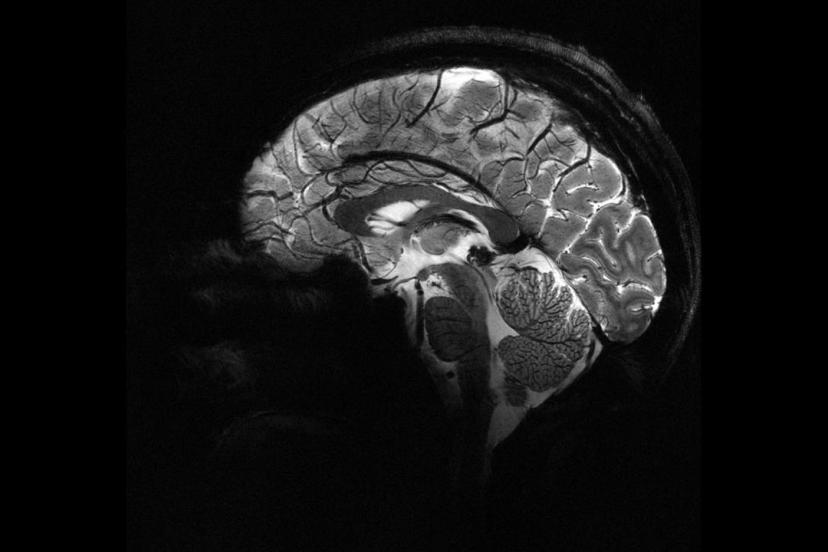

Beyne verilen elektrik akımı bencilliği azaltabilir mi?

Zürih Üniversitesi'nde yürütülen yeni bir araştırma, beynin iki farklı bölgesini uyararak, insanların daha az bencil olmalarını sağlamanın yolunu buldu.

Deney sırasında beynin ön ve arka kısımlarında yer alan frontal ve paryetal bölgelere elektrik akımı uygulandı. Bu iki bölge aynı anda uyarıldığında, katılımcıların daha fazla para paylaştığı gözlemlendi.